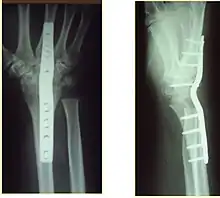

Surgery

Surgery is generally indicated for displaced or unstable fractures.[18] The techniques of surgical management include open reduction internal fixation (ORIF), external fixation, percutaneous pinning, or some combination of the above. The choice of operative treatment is often determined by the type of fracture, which can be categorized broadly into three groups: partial articular fractures, displaced articular fractures, and metaphyseal unstable extra- or minimal articular fractures.[5]

Significant advances have been made in ORIF treatments. Two newer treatments are fragment-specific fixation and fixed-angle volar plating. These attempt fixation rigid enough to allow almost immediate mobility, in an effort to minimize stiffness and improve ultimate function; no improved final outcome from early mobilization (prior to 6 weeks after surgical fixation) has been shown. Although restoration of radiocarpal alignment is thought to be of obvious importance, the exact amount of angulation, shortening, intra-articular gap/step which impact final function are not exactly known. The alignment of the DRUJ is also important, as this can be a source of a pain and loss of rotation after final healing and maximum recovery.

Surgical options have been shown to be successful in patients with unstable extra-articular or minimal articular distal radius fractures. These options include percutaneous pinning, external fixation, and ORIF using plating. Patients with low functional demand of their wrists can be treated successfully with nonsurgical management; however, in more active and fit patients with fractures that are reducible by closed means, nonbridging external fixation is preferred, as it has less serious complications when compared to other surgical options.[5] The most common complication associated with nonbridging external fixation is pin tract infection, which can be managed with antibiotics and frequent dressing changes, and rarely results in reoperation.[5] The external fixator is placed for 5 to 6 weeks and can be removed in an outpatient setting.[5]

If the fractures are unlikely to be reduced by closed means, open reduction with internal plate fixation is preferred.[5] Although major complications (i.e. tendon injury, fracture collapse, or malunion) result in higher reoperation rates (36.5%) compared to external fixation (6%), ORIF is preferred, as this provides better stability and restoration of the volar tilt.[5][23] Following the operation, a removable splint is placed for 2 weeks, during which time patients should mobilize the wrist as tolerated.[5]